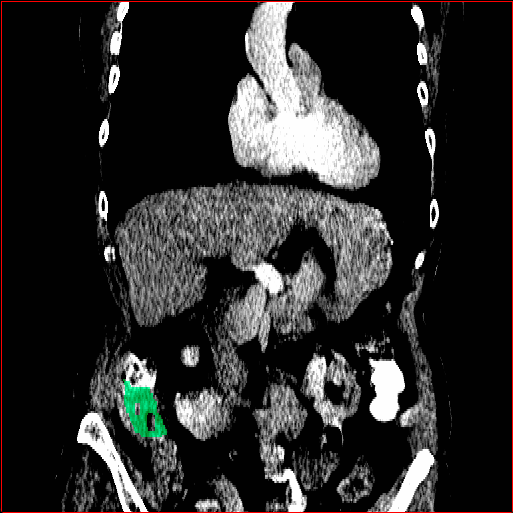

Colon Tumor

0.75×0.75×1.50.75\times 0.75\times 1.5

mm

512×512×256512\times 512\times 256

Figure 4: MAISI-v2 segmentation-guided results for five types of tumors. We show results for different voxel spacing and volume size to demonstrate the flexibility of MAISI-v2. Different Hounsfield Unit window is used to better show the contrast between tumor and normal tissues.